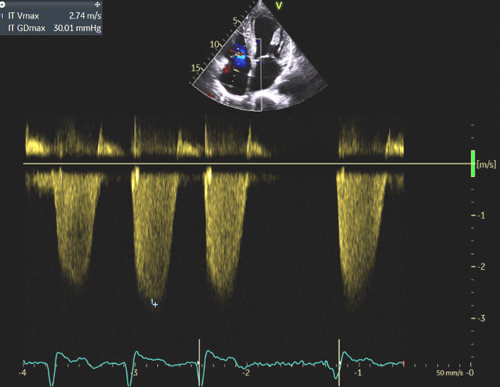

La dilatation des oreillettes est fréquente et s’associe à une dysfonction diastolique. Les pressions de remplissages VG sont souvent élevées (Figure 2) sauf à un stade préclinique chez certains patients a- ou peu symptomatiques. L’étude de la fonction diastolique ventriculaire gauche est basée sur une approche multiparamétrique intégrant le Doppler pulsé mitral, le DTI à l’anneau mitral, le volume de l’oreillette gauche (>32-34 ml/m² SC) et la Vmax du flux d’IT (>2.8 m/s) permettant également d’estimer les pressions artérielles pulmonaires (PAPS).

Figure 2 : Pressions de remplissage VG élevées souvent élevées en cas d’amylose cardiaque évolutive.

Exemple de pressions de remplissages élevées chez un patient avec amylose cardiaque : E/A >2, E/E’ moyen = 13, volume biplan indexé de l’OG > 34 ml/m² SC, Vmax de l’IT proche de 2.8 m/s